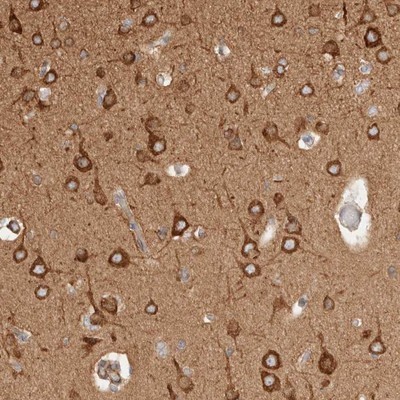

Supportive validation

- Submitted by

- Novus Biologicals (provider)

- Main image

- Experimental details

- Immunohistochemistry-Paraffin: RRP15 Antibody [NBP1-84522] - Staining of human cerebral cortex shows strong cytoplasmic positivity in neuronal cells.